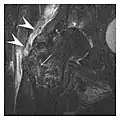

- a

- b

Figure 13: Partial osseous avulsion of the gluteal muscles at the greater trochanter in a 59-year-old man who presented with the right hip pain without a history of trauma. Lauenstein view and anteroposterior and radiographs (not shown) did not show an obvious fracture line or disruption of bony contours in the acetabulum or the right femoral neck. (a) Coronal T1-weighted MRI displays an incomplete fracture line extending partially from the greater trochanter (arrow). (b) Coronal short tau inversion recovery MRI shows heterogeneous hyperintensity in the same region (arrow) as well as hyperintensity within the gluteus medius and minimus muscles (arrowheads) consistent with tissue edema and hematoma.[1]